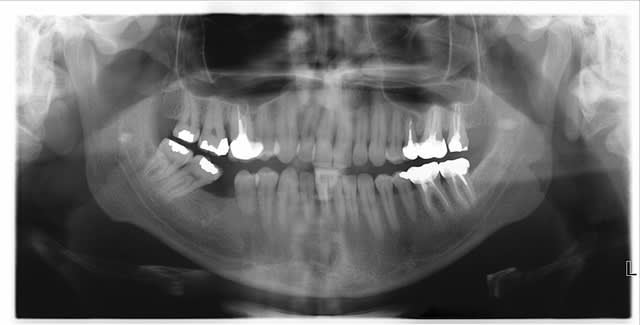

Je relance le sujet, pour savoir comment vous traiteriez cette petite carie sous-gingivale sur 47 ?

Tu ne vois que la carie ?

Je vois une résorption importante de 45, une 46 absente, et une 47-48 qui se couchent

Non je ne vois pas que ça, d'ailleurs il a une poche paro de 10mm qu'on ne voit pas très bien autour de la 16, en plus de toutes tes observations.